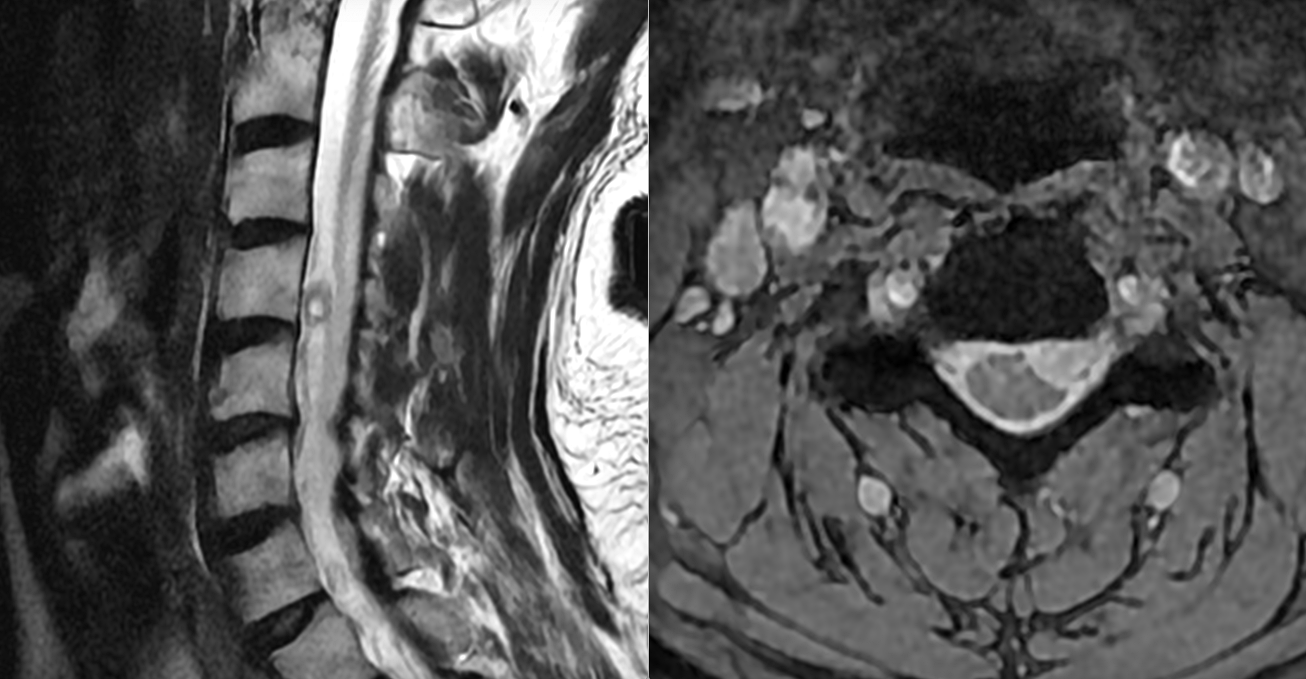

Tumoră intramedulară toracală – ependimom

Schwannom radicular C5 stânga

Meningiom spinal toracal cu compresiune medulară severă